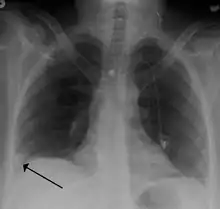

- Chest X-rays are often done on people with shortness of breath to help rule-out other causes, such as congestive heart failure and rib fracture. Chest X-rays in PE are rarely normal,[61] but usually lack signs that suggest the diagnosis of PE (for example, Westermark sign, Hampton's hump).